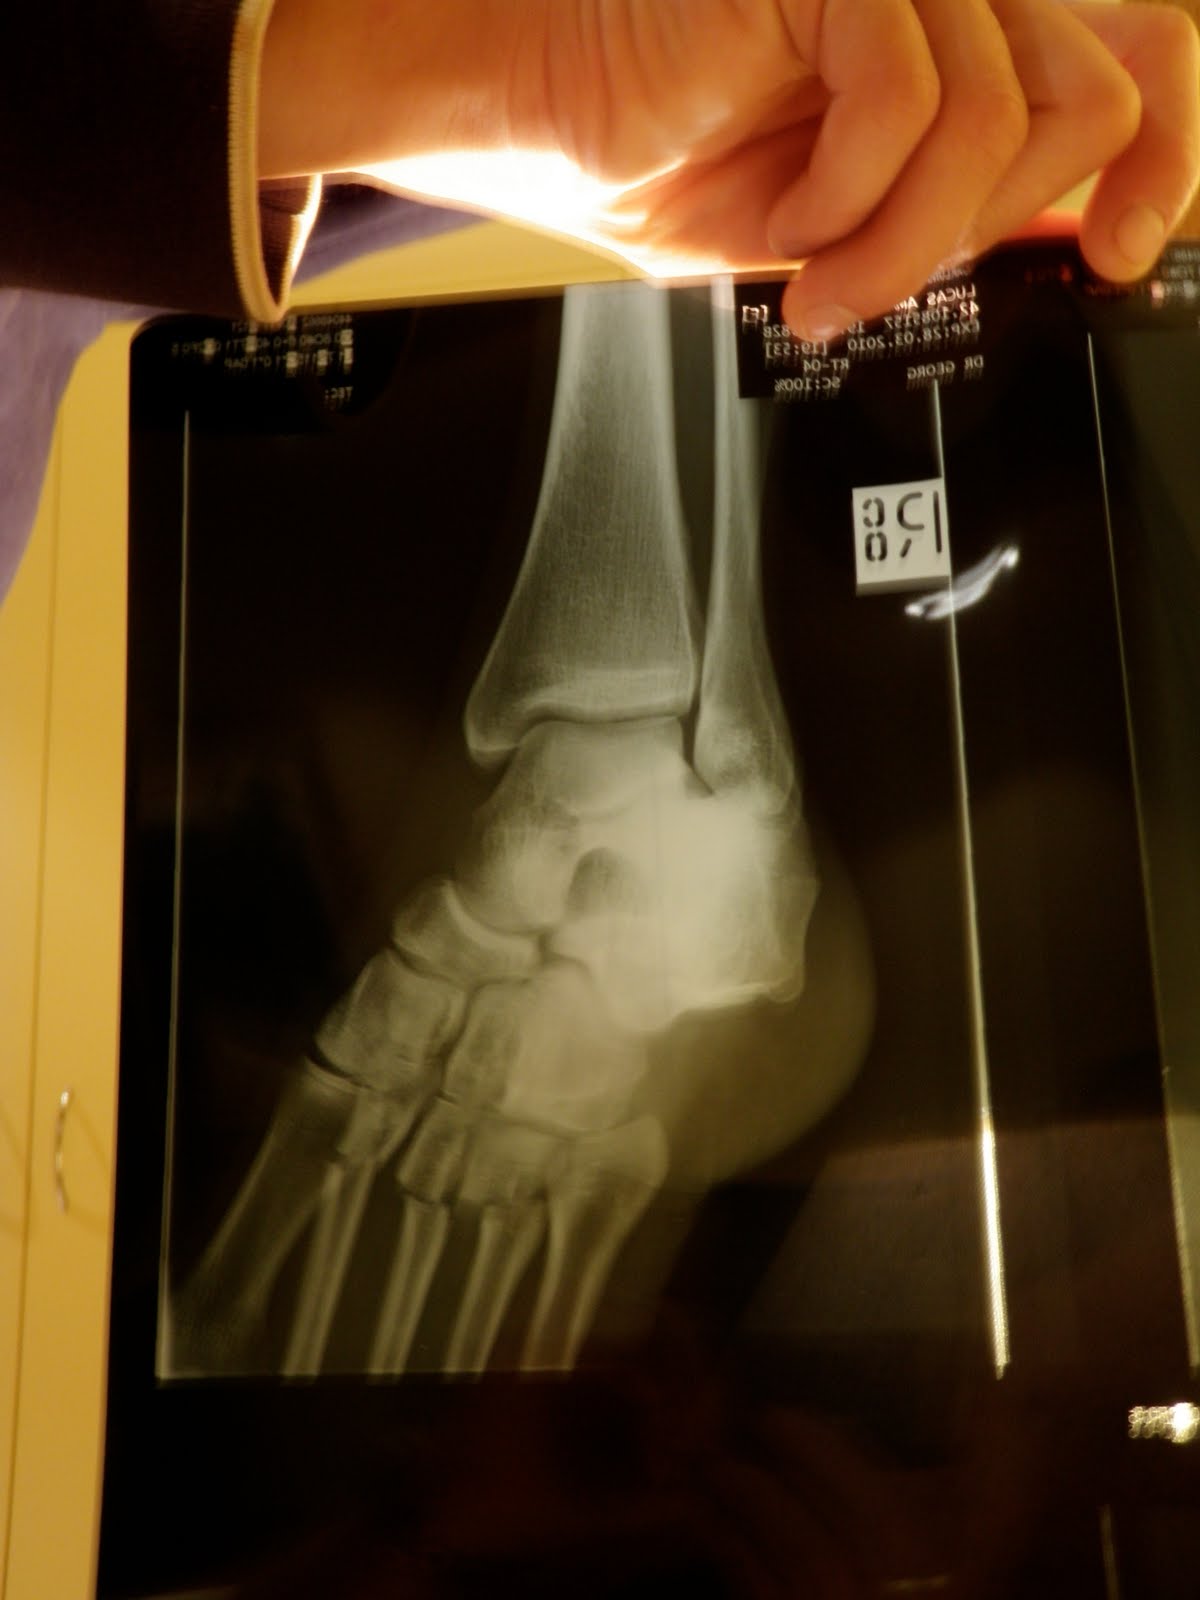

X Ray

My fractured foot....

After about an hour and a half in the waiting room, and me being in pain, I was finally called in, where we waited again to see the nurse. She thought it was my ankle, but when I told her what happened and where the pain was, she said it warranted an xray.......um, yeah!!!!! The doc came by, had a look, gave me shit for taking 800 mg of motrin - whatever, it was a one time dose and my foot freakin' hurt! He ordered some more pain killers which it took forever for me to get, and ordered some xrays. A couple of the positioning of my foot sent pains all through my foot and ankle, at one point the xray tech whispered "I think you have a few broken bones", which she later confirmed after looking at them all - but shhhhh, she didn't tell me that!! My foot was plantarflexed and I couldn't move it up, I couldn't move my toes and to even touch them sent pains everywhere. After the painful xrays I got 1 percocet (endone as they call it here) which after about 45 minutes I could feel relief, thank goodness! The doctor confirmed the broken bones, three of them, 2nd, 3rd, and 4th metatarsal, mid-foot. (Once I get a bit better and can get some help, I'll see if I can take a picture of the Xray.) The ER doc consulted the orthopedic surgeon, we where to put a half slab (half cast) on my foot to stabilize it, and we didn't have to move my foot, which I was terrified of. I am to see the ortho team at the main hospital on Wednesday, they will re-Xray it, if the bones haven't moved they will plaster my whole foot, but if the bones have shifted I may have to have surgery :( another thing that I have not had before, well, that I can remember anyways.

The ortho surgeon, who I can't remember his name, was very nice, and he even had a small team come in with him - I guess it was a pretty cool fracture. They are more or less curious as to why my foot is SO swollen, and they where even querying a dislocation. The dislocation was later ruled out by looking at my other foot and realizing that it is 'just me' :) The doctor is also concerned that I may have damaged a ligament that runs along my 'big' metatarsal which basically holds all the other metatarsals together (think of your finger bones, and there is a ligament that holds them all together), which may be causing the swelling. If this is damaged or pinched, surgery will be required. BUT, in order to get a better look, a CT would need to be done. Today's X-rays showed that it is getting better, so the CT is put on hold. I am to return in a week for a repeat xray, and then, well, we'll go from there.